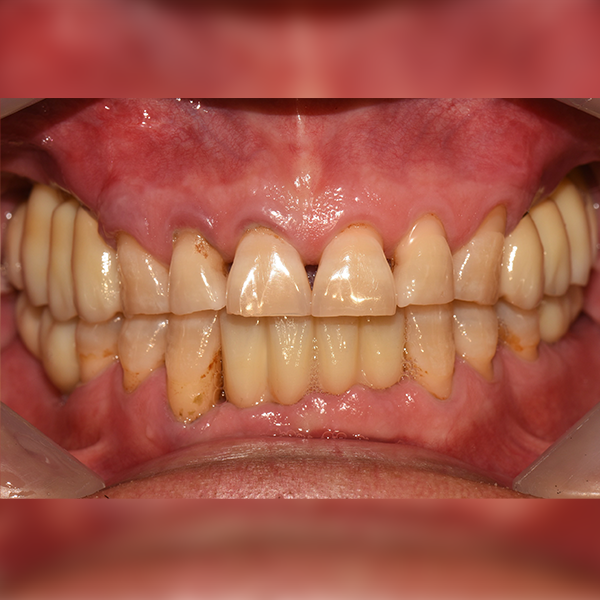

3. Trường hợp 239 Ông/Bà Lee*gan, 50 tuổi 2019-01-11 / 2019-07-24

Trường hợp 239 Ông/Bà Lee*gan, 50 tuổi 2019-01-11 / 2019-07-24

Before Before

After After